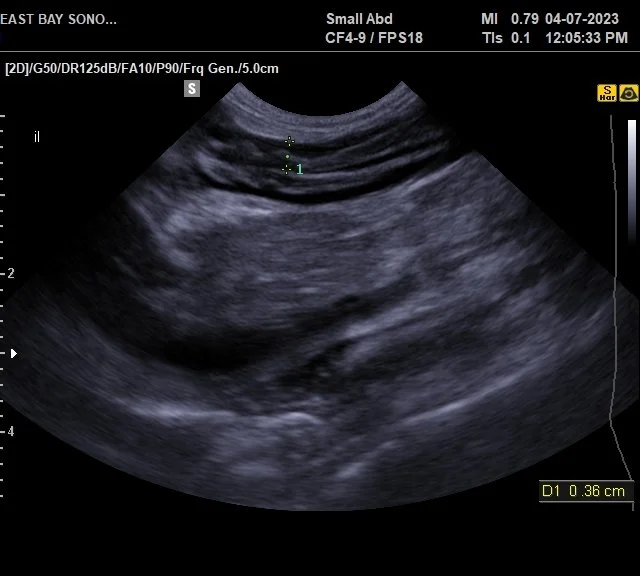

Animals Free FullText BMode and Contrast Enhanced Ultrasonography How Do You Test For Ibd In Cats your vet may recommend an abdominal ultrasound and/or a biopsy of the small intestine. A biopsy is the only way to confirm ibd. it has been shown that cobalamin supplementation improves clinical signs in cats with gi disease regardless of the. Diagnosis of ibd is based on the signs and symptoms listed above, a thorough history where your. How Do You Test For Ibd In Cats.